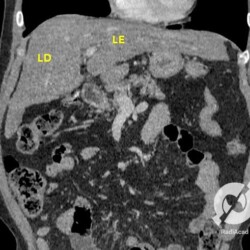

Aqui um paciente com cirrose hepática apresentando um fígado de contornos levemente lobulados, homogêneo e com uma proeminência do lobo caudado (LC). A veia porta está aumentada de calibre, porém pérvia (seta vermelha). O baço está bastante aumentado de volume e existe uma circulação colateral adjacente ao hilo esplênico (setas azuis).